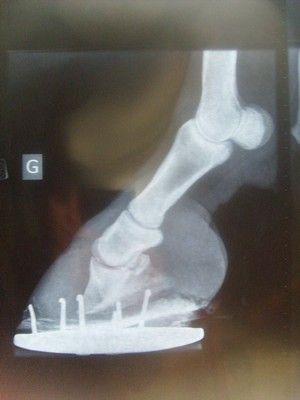

| Dire merci | pour vous expliquer un peu le cas de ma ponette; elle a une grave fourbure aux antérieurs sans présence de boiterie (je l'aie achetée comme ça). elle a eu un seul mauvais ferrage qui pour moi a entrainer sa boiterie actuelle, ensuite elle a eu sur avis véto une ferrure à l'envers plus plaques, qui ne l'ont soulagés qu'un temps. Les ferrages se passant de plus en plus mal, j'ai décidé de la passer pieds nus, depuis elle revit si je puis dire, elle retrotte galope d'elle même, la boiterie a disparu sur le mou, mais elle reste quand même tréés sensible sur le dur. On en ai qu'au début du parage naturel, c'est son 3ème parage, même si l'on voit beaucoup de progrès au niveau de ses pieds et de locomotion, ma pareuse m'a conseillé de poser le PWH car le soucis de kétie est mécanique, tant qu'elle ne posera pas bien son pieds sa pousse ne sera pas bonne. pour illustrer un peu ( radio de l'antérieur le plus atteint) ![]() donc au prochain parage kétie aura sur ses petits petons des PHW, j'espère sincérement que cela va l'aider, j'ai envie d'y croire, d'ou mes demandes de témoignages lol. bientôt 8mois qu'elle se bat, j'ai envie de croire que cela est bientôt fini pour elle, car elle le mérite cette naine |

| Dire merci | Vous avez des autres radios prises sur la profile? Le radio inclu dans votre commentaire n'a pas beaucoup d'intéret. Pour Ameca, je ne partage vous opinions basé sur un cas et encore, il faudra bien voir le pied avant. Quelque part il y a une manque de bon sens et objectivité. Je voudrais dire que j'utilise rarement PHW parce que j'arrive de changer les habitudes des propriétaires face à les problèmes de pieds de leur chevaux. Par contre, les fois ou je les utilisaient (peut être 'hoofcast ou autre system de platrage pourrait donner la même resultat), la bénéfice est inconstestable et le cheval à recupéré nettement plus vite avec moins de souffrance que sans. Je n'ai aucun connection avec LaPierre et companie mais les produits de chez eux sont bien et bien étudiés (contrairement à la majorité des produits en vente actuellement pour soins les chevaux). |

| Dire merci | Je n'ai que des radios de profil en ma possession. |

| Dire merci | Bon, ce radio est mal prise (pas en axe). |